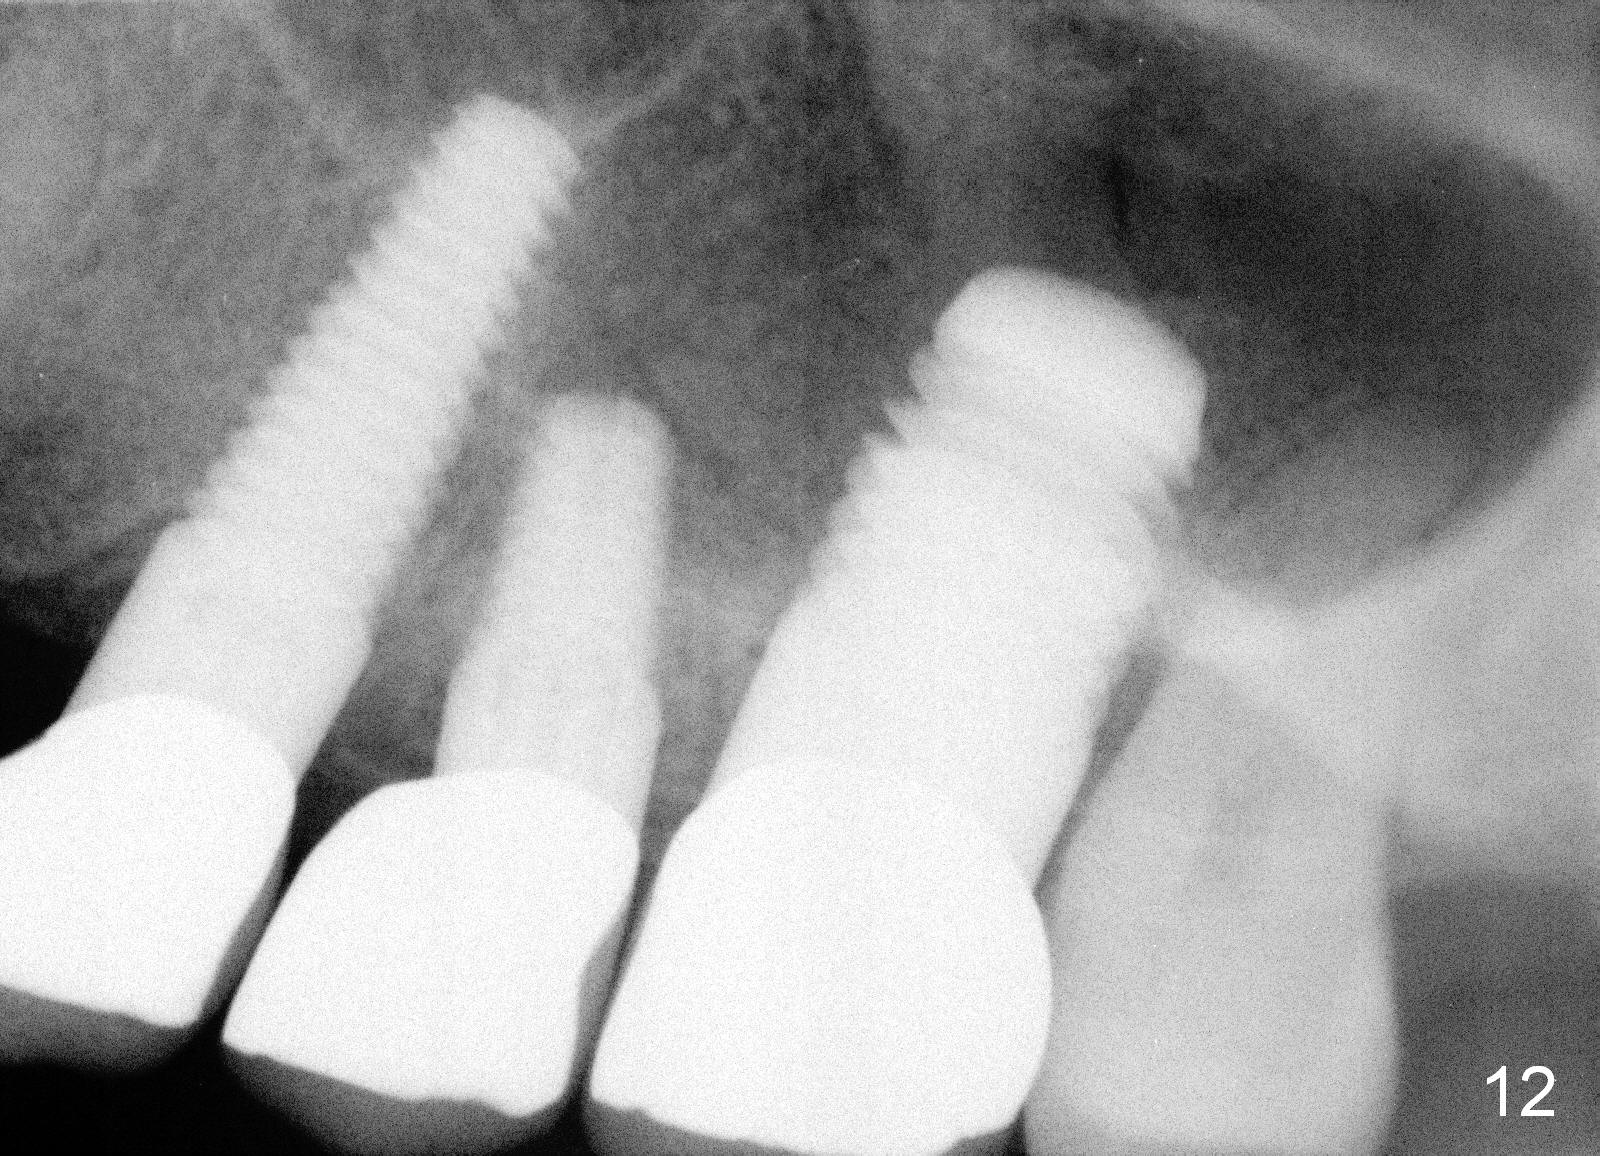

Anyway, three of the implants heal normally 3 months postop (Fig.10) and restore together. Fig.11 and 12 are taken 11 and 21 months post cementation.